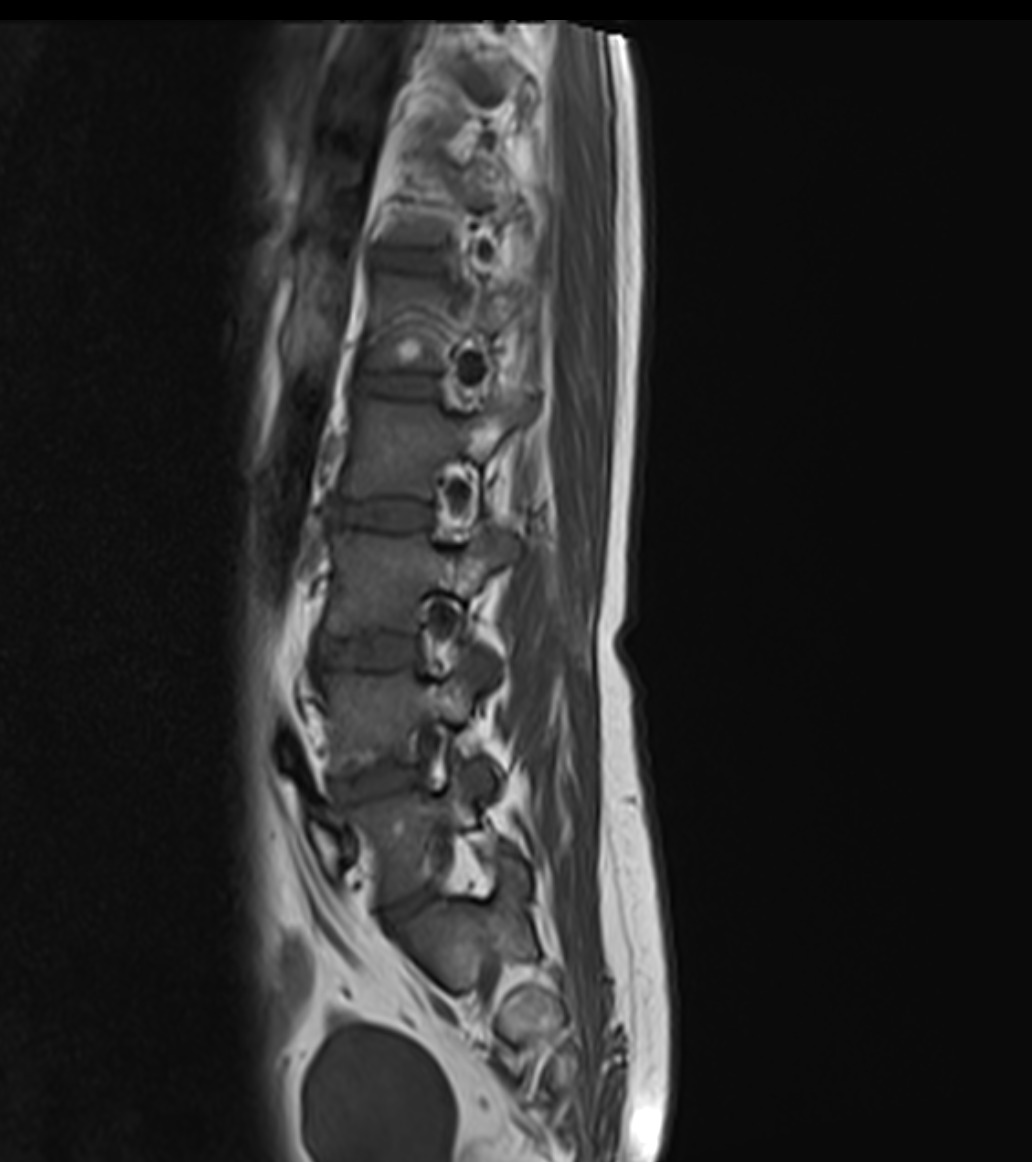

Resonancia Magnética de columna lumbar

“QUISTES PERINEURALES”

Los quistes perineurales son quistes llenos de líquido cefalorraquídeo en las raíces nerviosas, localizados principalmente en la zona sacra de la columna vertebral, aunque pueden encontrarse en cualquier sección de la columna vertebral; pueden causar una radiculopatía progresivamente dolorosa. Las mujeres se ven afectadas con mayor frecuencia que los hombres. Los pacientes con quistes perineurales presentan dolor en la zona de los nervios afectados por el quiste, debilidad muscular, dificultad para sentarse durante periodos prolongados, pérdida de la sensibilidad, pérdida de reflejos, dolor al estornudar o toser, inflamación en la zona sacra, parestesias, dolor de cabeza, ciática, y disfunción intestinal, de vejiga y sexual.

El diagnóstico se basa en la resonancia magnética.